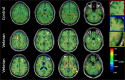

Traumatic brain injury (TBI) is a risk factor for the later development of neurodegenerative diseases that may have various underlying pathologies. Chronic traumatic encephalopathy (CTE) in particular is associated with repetitive mild TBI (mTBI) and is characterized pathologically by aggregation of hyperphosphorylated tau into neurofibrillary tangles (NFTs). CTE may be suspected when behavior, cognition, and/or memory deteriorate following repetitive mTBI. Exposure to blast overpressure from improvised explosive devices (IEDs) has been implicated as a potential antecedent for CTE amongst Iraq and Afghanistan Warfighters. In this study, we identified biomarker signatures in rats exposed to repetitive low-level blast that develop chronic anxiety-related traits and in human veterans exposed to IED blasts in theater with behavioral, cognitive, and/or memory complaints. Rats exposed to repetitive low-level blasts accumulated abnormal hyperphosphorylated tau in neuronal perikarya and perivascular astroglial processes. Using positron emission tomography (PET) and the [18F]AV1451 (flortaucipir) tau ligand, we found that five of 10 veterans exhibited excessive retention of [18F]AV1451 at the white/gray matter junction in frontal, parietal, and temporal brain regions, a typical localization of CTE tauopathy. We also observed elevated levels of neurofilament light (NfL) chain protein in the plasma of veterans displaying excess [18F]AV1451 retention. These findings suggest an association linking blast injury, tauopathy, and neuronal injury. Further study is required to determine whether clinical, neuroimaging, and/or fluid biomarker signatures can improve the diagnosis of long-term neuropsychiatric sequelae of mTBI.